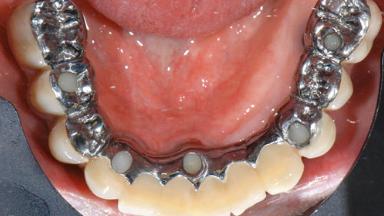

A 77-year-old male patient was referred for the management of frequent and repeated acrylic fracture of his existing mandibular fixed full-arch implant-supported metal/acrylic prosthesis. He also complained about softtissue soreness and the lack of retention and stability of his maxillary removable partial metal/acrylic prosthesis. Both prostheses had been delivered two years previously as part of his full-mouth rehabilitation (caries, tooth wear, tooth fracture). His medical history revealed high blood pressure, controlled with the use of antihypertensive medication.

Defining Characteristics Fully edentulous lower jaw to be rehabilitated with an implant-borne fixed dental prosthesis

Retention Screw-retained, with 4 or more splinted implants Screw-retained, with 4 or more splinted implants